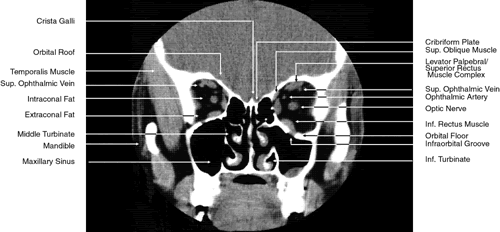

The globe is shown in Figure 12. The orbit and periorbital structures are shown in Figures 13 through 16, and the optic canal is shown in Figures 17 through 26. The cavernous sinus and optic chiasm are shown in Figures 27 and 28, and the posterior visual pathway and cranial nerves are shown in Figures 29 through 33.

Fig. 17. Coronal images through anterior orbit. A. Computed tomography scan. B. T1-weighted magnetic resonance imaging.

Fig. 18. Coronal images through midglobe. A. Computed tomography scan. B. T1-weighted magnetic resonance imaging.

Fig. 19. Coronal images through midorbit posterior to the globe. A. Computed tomography scan.B. T1-weighted magnetic resonance imaging.

Fig. 20. Coronal images through orbital apex. A. Computed tomography scan. B. T1-weighted magnetic resonance imaging. C. Anatomic section of a cadaver head at the level of the orbital apex.

ORBIT AND PERIORBITAL STRUCTURES

The bony orbital and periorbital anatomy is best visualized with CT, whereas the soft tissue anatomy can be visualized with either CT or MRI. The orbital cavities are roughly shaped like quadrilateral pyramids parallel to each other medially and lying on one side with their apex facing posteriorly. The widest portion of the orbit is approximately 1.5 cm posterior to the orbital rim (see Fig. 2). On average the adult orbit is 40 to 45 mm deep, with the anterior orbit measuring 40 mm wide and 35 mm high. The interorbital distance in the normal adult is 25 mm. In contrast, the newborn orbit is more rounded, with a width and height of 27 mm, and the orbit of a 7-year-old measures 28 mm high and 33 mm wide.48 The orbital volume is approximately 30 mL, in comparison to the globe, whose diameter of24 mm gives it a volume of 6.5 to 7.0 mL.